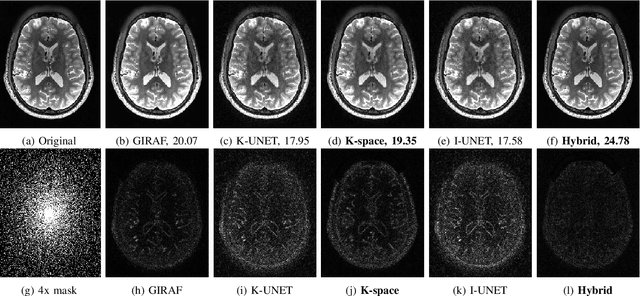

Abstract:We introduce a fast model based deep learning approach for calibrationless parallel MRI reconstruction. The proposed scheme is a non-linear generalization of structured low rank (SLR) methods that self learn linear annihilation filters from the same subject. It pre-learns non-linear annihilation relations in the Fourier domain from exemplar data. The pre-learning strategy significantly reduces the computational complexity, making the proposed scheme three orders of magnitude faster than SLR schemes. The proposed framework also allows the use of a complementary spatial domain prior; the hybrid regularization scheme offers improved performance over calibrated image domain MoDL approach. The calibrationless strategy minimizes potential mismatches between calibration data and the main scan, while eliminating the need for a fully sampled calibration region.